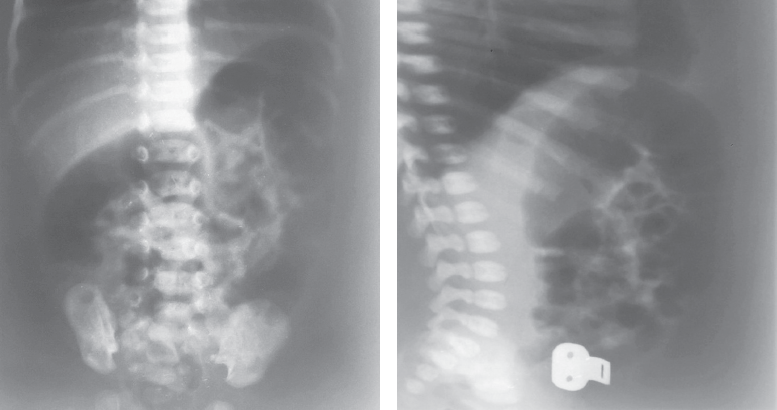

Hirschsprung’s disease usually manifests from the first days of life and is diagnosed in the newborn period. In some patients Hirschsprung’s disease can’t be diagnosed in the newborn period because of different forms of disease and clinical features. From 2008 to 2019 75 patients with Hirschsprung’s disease were operated in the City Children’s Hospital No. 1. 21 patients had delayed diagnosis. 11 newborns didn’t have very clear clinical symptoms, intestinal obstruction disappeared after decompression. 2 patients with associated chromosomal disorders were diagnosed with Hirschsprung’s disease later because of. In some of older patients disease manifested with severe constipations. Also, we presented some clinical cases of major diagnostic errors in patients with Hirschsprung’s disease. Conclusion. Diagnostic errors in patients with Hirschsprung’s disease are associated with the lack of alertness of neonatologists and inadequate interpretation of clinical manifestations and X-ray study. For many years these children can be treated by different specialists before having surgical consult.